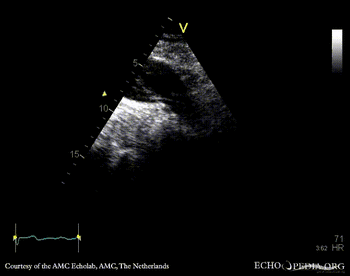

Aortic dissection type A

PLAX: dilated aortic root, dissection flap in ascending aorta PLAX: diameter of aortic root